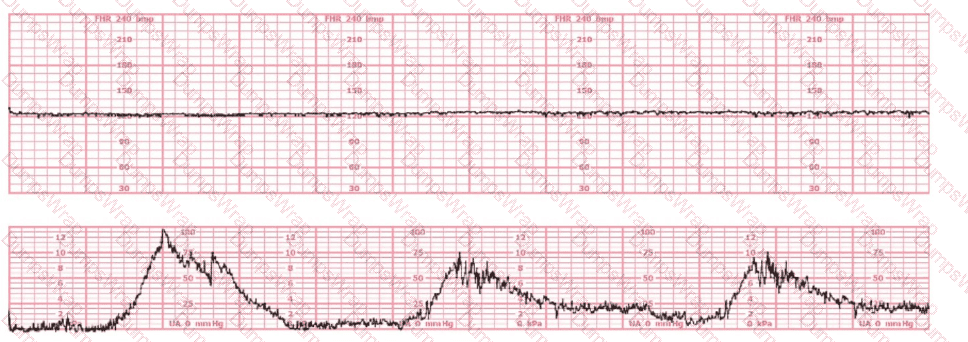

The tracing shown is from a woman at 28-weeks gestation in the post-anesthesia care unit (PACU) after an appendectomy. She is alert and awake. Based on this fetal heart rate pattern, the most appropriate intervention is:

Options:

Administer terbutaline

Continued monitoring

Perform cesarean birth

Answer:

BExplanation:

Comprehensive and Detailed Explanation From Exact Extract–Based NCC C-EFM References:

The fetal heart rate tracing shows:

Baseline around 140 bpm

Minimal variability

No accelerations

No decelerations

Regular uterine activity but not tachysystole

This pattern is Category II, but in the context of:

28-week gestation

Immediate postoperative status after anesthesia

Maternal alertness and stability

NCC and AWHONN emphasize that maternal sedation, post-anesthesia effects, medications, and physiologic stress commonly cause temporary minimal variability without acidemia, especially at preterm gestations where baseline variability is normally lower.

Key NCC principle:

Minimal variability in a stable mother without decelerations does NOT require emergent delivery.

Instead, the fetus should be observed as anesthesia effects wear off.

Why other answers are incorrect:

A. Terbutaline – No tachysystole and no recurrent decels are present.

C. Cesarean birth – No bradycardia, no late decels, no absent variability, and no Category III criteria.

Thus, appropriate management is B. Continued monitoring.